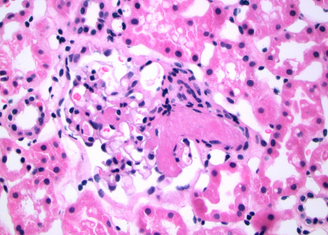

This patient has evidence of lung, kidney, and hematologic involvement with evidence of bleeding, as well as arterial and venous thrombosis all occurring within days. Additionally, she is anti-β2 glycoprotein I antibody positive and has histopathological evidence of vessel occlusion. The histopathology slide images from renal biopsy demonstrate a thrombosed small artery surrounded by renal tubules (Figure 2) and an arteriole at the base of a glomerulus with thrombosed glomerular capillaries (Figure 3).

An arteriole at the base of a glomerulus with a few thrombosed glomerular capillaries is seen (400× magnification). Surrounding tissues are renal tubules.